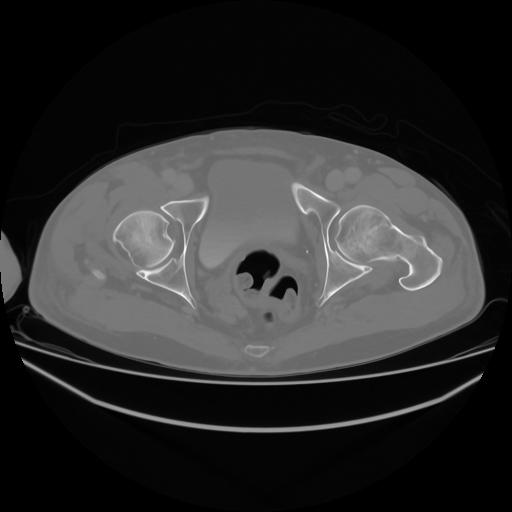

4 CUERPO,CE,Axial,3.0,CUERPO,,